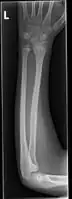

Front view of displaced fractured radius and ulna at wrist

Side view of displaced fractured radius and ulna at wrist